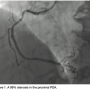

A 65-year-old male had a positive stress test and underwent diagnostic catheterization. The right coronary artery (RCA) demonstrated a stenosis of 40 to 50% with calcification and a distal 95 to 99% of the posterior descending artery (PDA) (Figure 1). Left main and left anterior descending coronary artery (LAD) were angiographically unremarkable, with mild irregularities. The left circumflex also demonstrated no significant stenosis and the second obtuse marginal (OM 2) had a 50% stenosis.